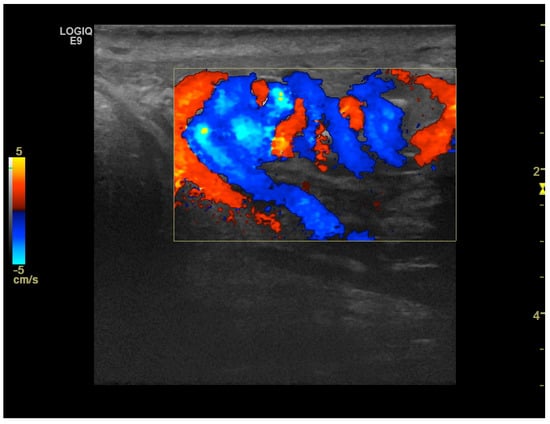

CD was employed to determine the vascularization of the mass. To maximize sensitivity to slow flow velocities, CD was performed using the highest signal gain setting possible (without the appearance of background noise) and low pulse repetition frequencies, allowing for the demonstration of peripheral lesional vascularity (Figure 3 and Video S2). A grade 4 varicocele was also diagnosed via Doppler sonography: dilatation of the veins of the pampiniform plexus around the testis to over 2.5–3 mm and backward flow toward the testes during Valsalva’s maneuver were observed (Figure 4).

Figure 4. Color Doppler image obtained using 15 MHz high-frequency transducer shows serpentine, dilated veins up to 2.5–3 mm in diameter at the inferior pole of the testis, which is consistent with a varicocele. In the spectral Doppler image, backward flow toward the testes during Valsalva’s maneuver was demonstrated (not shown).